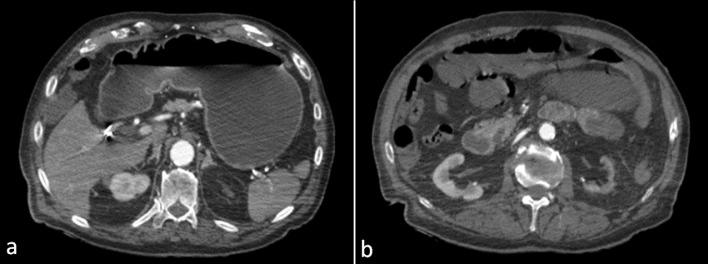

Acute Mesenteric Ischemia (AMI) is a rare life-threatening entity caused by sudden interruption of the blood supply to a segment of the bowel due to impairment of mesenteric arterial blood flow or venous drainage. Clinical presentation varies according to the time course of vascular occlusion. Contrast-enhanced Computed Tomography (CT) of the abdomen represents the main diagnostic test for AMI diagnosis, enabling fast and excellent evaluation of the intestine, mesenteric vasculature, and other ancillary characteristics of AMI. Typical CT findings of AMI include paralytic ileus, decreased or absent bowel wall contrast-enhancement, pneumatosis intestinalis, and porto-mesenteric venous gas. We hereby report a case of an 89-year-old man presenting with AMI due to Superior Mesenteric Artery (SMA) thrombotic occlusion following endovascular stenting superficial femoral arteries. Typical findings were observed on abdominal CT imaging, yet associated with the presence of gas exclusively in the SMA district, without any involvement of the porto-mesenteric venous system. Different imaging features and pitfalls can help radiologists to accurately diagnose AMI, especially when irreversible bowel damage is about to occur. Therefore, radiologists and emergency physicians should be aware of the unusual association between gas in the SMA arterial district and AMI, even in the absence of porto-mesenteric venous system involvement, in order to urge prompt surgical consultation when observed.

急性肠系膜缺血(AMI)是一种罕见的危及生命的病症,由肠系膜动脉血流或静脉引流受损导致肠段血液供应突然中断引起。临床表现根据血管闭塞的时间进程而有所不同。腹部增强计算机断层扫描(CT)是诊断AMI的主要检查方法,能够快速且出色地评估肠道、肠系膜血管系统以及AMI的其他辅助特征。AMI的典型CT表现包括麻痹性肠梗阻、肠壁强化减弱或消失、肠壁积气以及门静脉-肠系膜静脉积气。我们在此报告一例89岁男性患者,因股浅动脉血管内支架置入术后肠系膜上动脉(SMA)血栓形成闭塞而出现AMI。腹部CT成像观察到典型表现,但仅在SMA区域存在气体,门静脉-肠系膜静脉系统未受累。不同的影像学特征和陷阱有助于放射科医生准确诊断AMI,尤其是在即将发生不可逆肠损伤时。因此,放射科医生和急诊医生应意识到SMA动脉区域气体与AMI之间的异常关联,即使在门静脉-肠系膜静脉系统未受累的情况下,以便在观察到这种情况时促使及时进行外科会诊。